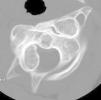

Se presenta una paciente de 11 años de edad que acudió al Servicio de Rehabilitación enviada por su pediatra por tortícolis resistente al tratamiento. En la exploración física se apreciaba una rotación de la cabeza hacia el lado derecho y una discreta flexión hacia el lado opuesto, con bloqueo de las rotaciones y las inclinaciones laterales, y con cierta flexo-extensión conservada. No existía compromiso neurológico. La familia recordaba un traumatismo leve 2 meses antes, con dolor de espalda varios días después, pero sin clara relación con el episodio actual. En la radiografía lateral de la columna cervical se apreciaba la masa lateral del atlas situada por delante de la apófisis odontoides (fig. 1). Posteriormente, se practicó una tomografía computarizada (TC) en la que se puso de manifiesto una rotación en el plano axial de C1 sobre C2, con luxación articular debida a la incongruencia de las carillas articulares de ambas vértebras (figs. 2 y 3), siendo el espacio atlo-odontoideo normal. La subluxación rotatoria de C1-C2 es una de las posibles etiologías de la tortícolis persistente, y aunque su frecuencia general es baja, es más habitual en niños1,2. El mecanismo lesional puede ser traumático o atraumático, siendo la mayoría de origen espontáneo3,4. Es muy frecuente que estos casos tarden en ser diagnosticados, por lo que ante una tortícolis resistente al tratamiento se debe sospechar, sobre todo si es precedido por un traumatismo leve1. La postura del paciente dificulta la exploración radiográfica, por lo que en estos casos está indicada la realización de una TC.